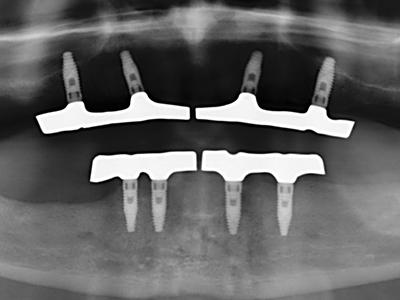

Bilder klinischer Anwendungsfälle

Bei der Knochenblockentnahme zeigen sich weitere Vorteile für die Piezochirurgie: Neben der bereits beschriebenen hohen Präzision bei der Osteotomie stellt sich gerade die Verwendung der dünnen Sägespitzen als besonders materialschonend heraus. Bei der Verwendung insbesondere von Lindemannfräsen sind mit deutlich höheren Entnahmeverlusten durch die dickere Instrumentenspitze zu rechnen (Lakshmiganthan, Gokulanathan et al. 2012). Die insbesondere bei retromolar entnommenen Blocktransplantaten notwendige basale Abtrennung wird durch speziell hierfür vorgesehene rechtwinklige Sägen erleichtert, so dass die Piezochirurgie als präzises, übersichtliches und sicheres Verfahren zur retromolaren Knochenblockgewinnung angesehen wird (Happe 2007) (Abb. 1-12).